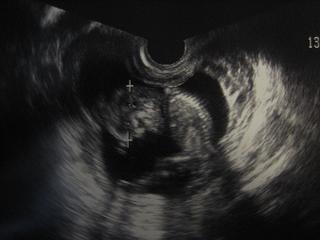

でも赤ちゃんはとっても元気です

今日も頭や足を元気に動かしてました

前回エコー写真をもらい忘れたので先生にお願いしたら

赤ちゃんの姿が分かりやすい体勢を選んで写真にしてくれました

とっても良い先生です

現在13w2d、頭の直径が2.8cm

背骨も足も見えてます